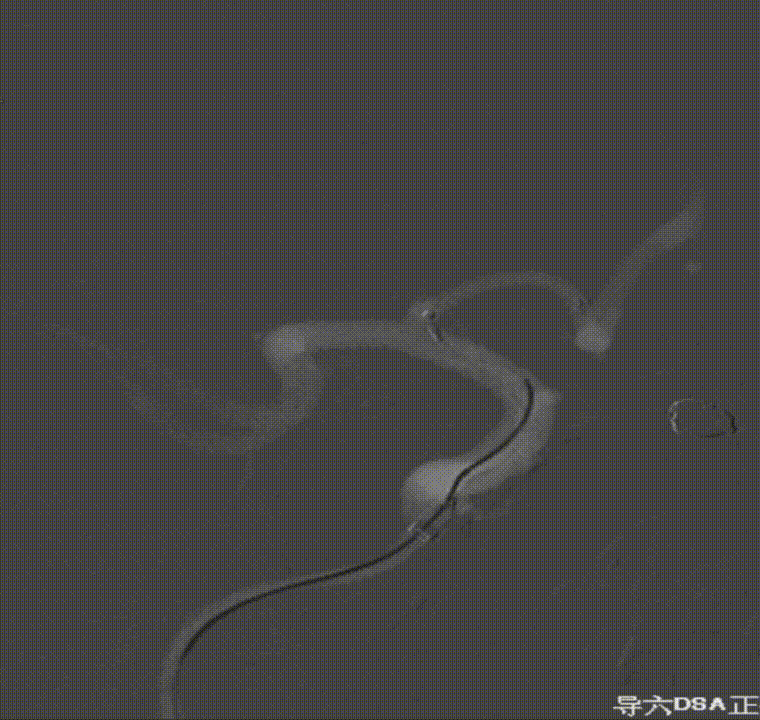

通过璞慧0.017微导管填入Target 1.5/2弹簧圈部分成篮,后释放Atlas 3.0/15支架覆盖瘤颈处,继续填入弹簧圈时微导管脱出,尝试用弹簧圈将微导管引导超选瘤腔失败。

撤出弹簧圈,Asahi 0.014微导丝引导璞慧 0.017微导管穿支架网孔进入动脉瘤内。

继续填入Target 1.5/2弹簧圈成篮,后完全释放支架,其近端位于颈内动脉分叉处,远端位于A1远端。

填入第一枚弹簧圈

通过调整栓塞微导管的张力继续填入Target 1/3弹簧圈。